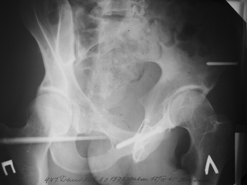

Диагноз : Сочетанная травма. ЗЧМТ. Перелом свода черепа. Ушиб головного мозга.Разрыв лонного и крестцово-подвздошного сочленений с нарушением целостности тазового кольца, с массивной забрюшинной гематомой и пропотеванием в брюшную полость. Перелом 10 ребра справа, осложненный гемопневмотораксом справа, правосторонней пневмонией на фоне ушиба правого легкого. Шок 3-4 ст. Больной поступил в отделение 07.03.2005г. в 16.00 в экстренном порядке через 30 минут после автодорожной травмы.Доставлен КСП. При поступлении состояние больного крайне тяжелое, явления травматического шока, А/Д-80/60 мм.рт. ст. ЧСС-120.В экстренном порядке поднят в операционную, интубирован, совместно с диагностическими мероприятиями лечение шока.При осмотре выявлены перелом 10 ребра справа, разрыв лонного и правого крестцово-подвздошного сочленений. Имеется линейный перелом теменной и височной костей слева с переходом на основание. Диагностическая лапароскопия 07.03.2005г. в 16.30-массивная забрюшинная гематома малого таза.Оставлена контрольная, дренажная трубка.Учитывая кровь в моче произведена цистография - данных за разрыв мочевого пузыря не найдено. Больной переведен в реанимационное отделение.За 08.03.2005г. из брюшной полости выделилось до 1500,0 мл, крови, часть крови реинфузирована. 08.03. в 06.30 наложен торокоцентез справа,удалено 100,0 мл. крови и 200,0 мл. воздуха .. Учитывая продолжающеееся кровотечение в брюшную полость из перелома костей таза, для исключения возможного разрыва внутренних органов 09.03.2005г. произведена Видеолапароскопия., на которой повреждения органов брюшной полости не выявлено.Одновременно произведен шов лонного сочленения проволокой и винтами, с одномоментным наложением стержневого аппарата на кости таза, с целью уменьшения кровотечения из разрывов тазовых сочленений, дренирование гематом. В последующем состояние больного оставалось тяжелым. 10.03.наложена нижняя трахеостома.Далее неоднократно производилась лечебно-диагностическая ФБС.С 10.03 выявлена правосторонняя плевропневмония. КТ головного мозга от 10.03-субарахноидальноекровоизлияние.Срединные структуры не смещены. КТ-контроль от 15.03-открытая моновентрикулярная гидроцефалия4 желудочка. Полисинусит. Постепенно состояние больного медленно прогрессировало к улучшению.С 24.03 переведен на самостоятельное дыхание, а 09.03 переведен в травматологическое отделение.Аппарат стержневой снят из-за перелома стержня (раскрутил больной самостоятельно).После госпитализации в наше отделение проведено дополнительное обследование Рентгекнография, КТ.Хотелось бы услышать Ваше мнение о дальнейшей тактике.-- С уважением, Leonid

Углядел билатеральное повреждение таза. Имеется вертикальная нестабильность со стороны перелома боковой массы крестца, ротационная с контрлатеральной стороны - чрезподвздошный разрыв кп сочленения. Разрыв лона, запирательные отверстия вроде целы.

DS. на сегодняшний день: Вертикальная двусторонняя нестабильная деформация таза, неправильно срастающийся перелом боковой массы крестца слева, срастающийся перелом крыла правой подвздошной кости, застарелый частичный разрыв правого кп сочленения, застарелый разрыв лонного сочленения.

План жизни - оперативное лечение. ЧКО таза (кольцевая опора), последовательная фиксация задних отделов с низведением перелома крестца, синтез лона пластинами, илиосакральное блокирование.